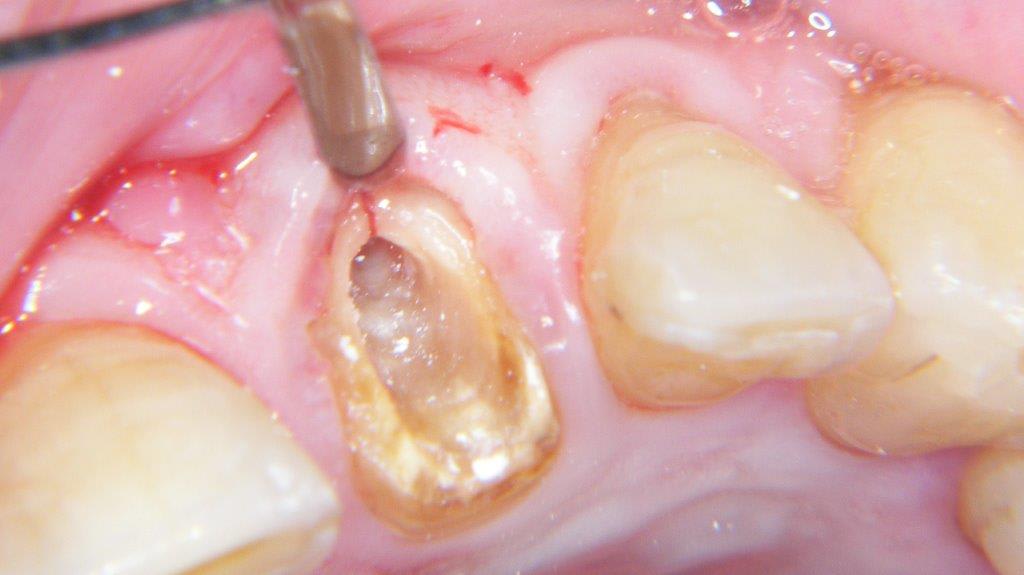

pour ceux que ça intéressent, une petite utilisation d'expansion de la paroi palatine, sur une avulsion d’incisive(racine fendue). toutes mes excuses pour la mauvaise qualité des photos.

Et à ton avis pourquoi ton incisive s'est fendue ? Y a qu'à regarder ta photo ...

Et donc tu mets un Implant dans ce contexte là .... faudra pas se demander pourquoi il y aura des complications prothétiques de type fracture de vis